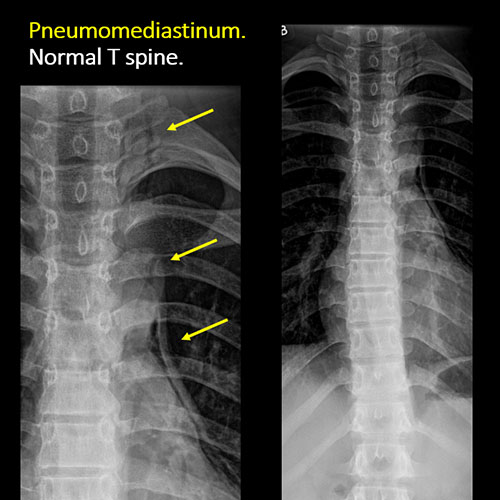

There is abnormality of the included lungs, mediastinum other than the previously evaluated paravertebral soft tissues, trachea and more distal airways, diaphragm, stomach, bowel, or bowel gas pattern. |

No | NA |

There is an oblique fracture with avulsion through the anterior inferior T9 vertebral body. The posterior elements are intact. There is excessive calcification of the anterior longitudinal ligament and there are continuous osteophytes in a pattern consistent with DISH (Diffuse Idiopathic Skeletal Hyperostosis).